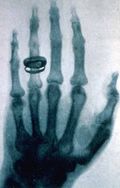

- 5 يناير - An Austrian newspaper reports that Wilhelm Röntgen has discovered a type of radiation later known as X-rays.

- 12 يناير - H. L. Smith takes the first X-ray photograph.

- January 18 - The X-ray machine is exhibited for the first time.